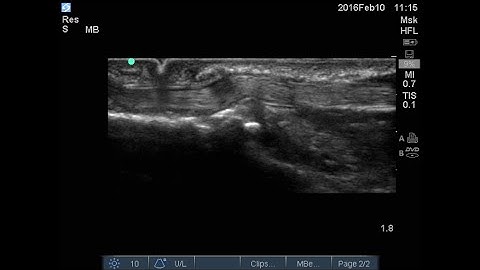

Trigger thumb demonstrated on ultrasound